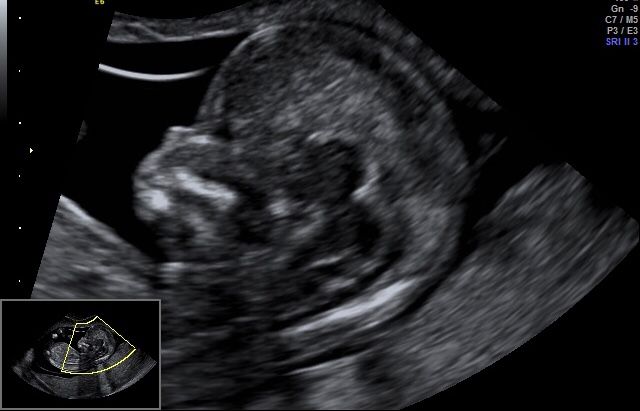

Certyfikowany ultrasonografista Fetal Medicine Foundation(FMF NT Specjalist) z uprawnieniami do wykonywania badań prenatalnych .

1.USG prenatalne wykonujemy pomiędzy 11 a 13 w 6 dni ciąży . Najlepsze rezultaty otrzymujemy gdy badanie przeprowadzamy pomiędzy 12 a 13 tygodniem ciąży . Pacjentka która chce aby badanie było bardziej szczególowe i w większym stopniu wykrywało wady genetyczne (82%vs 92 % wykrytych zespół wad genetycznych )powinna zgłosić się na wizytę z wynikiem tekstu PAPPA (test z krwi )

Jestem bardzo zadowolona z przebiegu wizyty. Pan doktor bardzo dokladnie i szczegolowo opisuje obraz usg. Wszystko zostało nam objaśnione. Badanie wykonywane na wysokiej jakości sprzęcie. Dodatkowo obejrzelismy maluszka w obrazie 4D. To bylo badanie prenatalne III trymestru, żałuję ze poprzednie dwa badania prenatalne zostały wykonane w innym gabinecie.